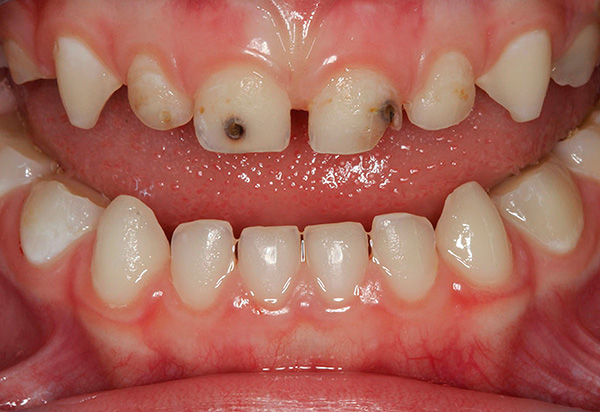

A situação mais comum está relacionada à odontologia pediátrica, quando os pais de crianças com uma lesão cariosa de um dente de leite (temporário) exigem urgentemente que um dente seja retirado, acompanhado por algo assim: “De qualquer forma, ele cai - por que tratar?”.

Essa lógica é muito direta e não leva em conta o fato de que a substituição dentária normalmente deve ocorrer na idade apropriada: grupos simétricos de dentes gradualmente se tornam móveis e, em muitos casos, caem sozinhos. Se o dente é removido prematuramente (mesmo um ano antes), existe um alto risco de má oclusão e o desenvolvimento de anomalias na erupção de dentes permanentes.

Em outras palavras, com a remoção precoce dos dentes de leite (especialmente múltiplos), os dentes permanentes futuros podem literalmente "se separar" em diferentes direções, ou mesmo não irromper em uma versão única ou em grupo. Nenhum pai são precisa de tal perspectiva, por isso é melhor agora salvar a criança da intervenção cirúrgica, curando a cárie dentária ou suas complicações, do que investir energia e dinheiro na correção da oclusão e da psique da criança.